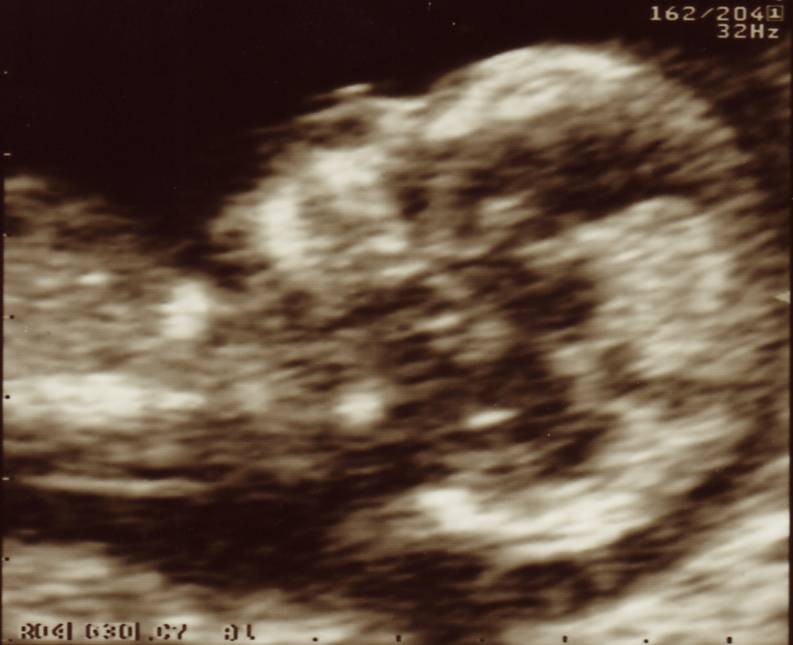

4D Scan Photos

A nuchal scan close-up. Just look at the size of that brain. She has a nasal bone too, which is actually quite important.